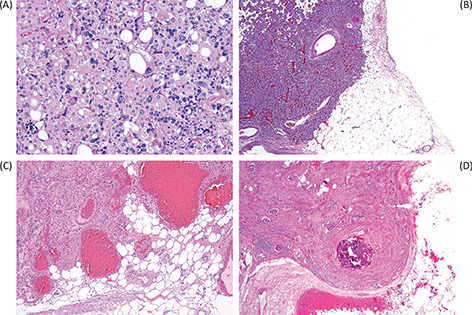

The characteristic gross appearance of oncocytoma includes a tan or mahogany brown cut surface (2, 68), generally similar to normal renal parenchyma in color and in contrast to the golden yellow cut surface of clear cell renal cell carcinoma. Although a central scar is quite characteristic of oncocytoma (Figure 1A), it is not specific for oncocytoma and is not present in all tumors (2, 68). A central scar can also be found in chromophobe renal cell carcinoma, as well as other slow growing neoplasms, and substantial hyalinization and fibrosis can also be present within clear cell renal cell carcinoma. With the increasing identification of renal masses incidentally via imaging techniques, the size of oncocytoma tumors can also range from small solid nodules without central scar to large masses that would otherwise be concerning for high-stage renal cell carcinoma.

Fig 1

Figure 1. The characteristic gross appearance of oncocytoma (A) varies depending on the size of the tumor, but often has a similar color to normal renal parenchyma (mahogany brown) and characteristically, but not consistently, a central scar. Microscopic appearance typically includes nests dispersed in fibrous stroma (B) and can include tubular structures (C) or densely packed nests (D). Immunohistochemical staining for CK7 can be increased in the central scar area (E) but is typically limited to only scattered cells and small clusters of cells in other areas (F).

The classic histologic appearance of renal oncocytoma includes nests and tubular structures lined by cells with eosinophilic, granular cytoplasm (Figure 1B–D). Uncertainty in the diagnosis can arise when other patterns are present, such as a highly compact nested architecture, resulting in an almost entirely solid appearance, or when small papillary structures protrude into cystic spaces, raising concern of an eosinophilic variant of papillary renal cell carcinoma. Oncocytomas typically contain edematous myxoid or hyalinized stroma, often resulting in at least some areas with nests and tubular structures dispersed in this stroma. Clear cytoplasm may also be focally present, typically in the area of the central scar.